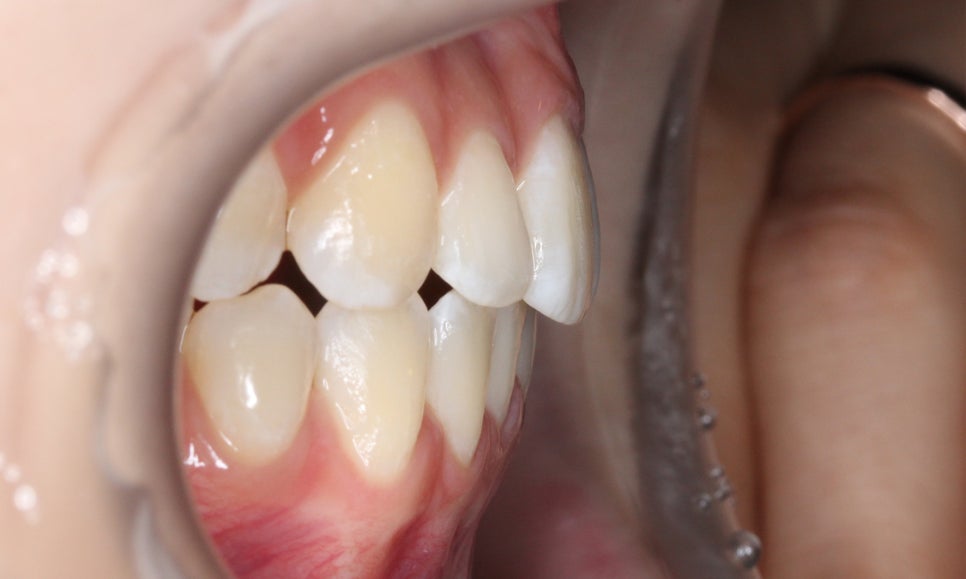

overbite 사진에서도 상하악이 벌어진 부분 없이

바르게 교합되고 있는 모습으로

자가결찰브라켓을 적용하였기 때문에

단기간에 교정을 마무리할 수 있었습니다.

신논현치과 환자분의 교정 후 overjet 사진입니다.

교정 전에도 전치부의 돌출감은 그다지

심하지는 않았지만 교정 후 조금 더

가지런해지고 반대교합 증상을 보이던

측절치가 올바르게 교합되면서

전치부의 심미성이 보완된 모습입니다.

좌우의 교합 평면을 보면 협측의 치아 배열이

교정 전보다 가지런해진 것을 확인할 수 있는데요,

비발치로 교정을 진행하였기 때문에

전체적인 악궁의 길이는 짧아지지 않고

삐뚤어진 치아들만 바르게 배열된 모습입니다.

하악 또한 상악과 같이 전치부에서

발견되던 crowding이 사라졌고

치열이 가지런하게 바뀐 모습을 확인할 수 있는데요,

신논현치과에서는 위와 같은 부분적인

부정교합을 단기간에 심미적으로 교정할 수 있는

다양한 교정 방법을 연구하여 발전시키고 있습니다.

따라서 일반적으로 교정에 소요되는 시간보다

1~3개월 정도 단축하여 교정을 마무리하실 수 있는데요,

오늘 소개해드린 클리피씨교정의 경우 평균적인

교정기간이 1년 내외이기 때문에 빠른 교정을

원하시는 경우 적용이 가능합니다.